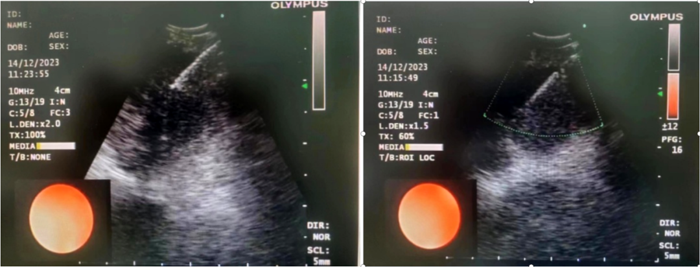

病例1

患者,女,72歲,2月來“反復(fù)咳嗽、咳痰,偶咳白痰中帶血絲”,胸部CT提示“肺占位、肺炎”,收住院。完善胸部強(qiáng)化CT提示“左肺占位、肺炎、縱膈多發(fā)淋巴結(jié)腫大”,電子支氣管鏡檢查見左肺上葉支氣管血塊及壞死物阻塞,清除后見管腔通暢,刷檢DNA細(xì)胞學(xué)示“細(xì)胞退變明顯,建議進(jìn)一步檢查”。10月27日行CT引導(dǎo)下肺穿刺活檢,病理示“機(jī)化性肺炎”,給予抗感染及激素治療,患者癥狀好轉(zhuǎn)出院。半月前,患者復(fù)查肺CT發(fā)現(xiàn)病灶較前稍有增大,張強(qiáng)主任考慮患者癥狀雖有好轉(zhuǎn),但仍存在腫瘤性病變可能性。經(jīng)過討論及與患者家屬充分溝通后,決定實(shí)施支氣管內(nèi)超聲引導(dǎo)下針吸活檢術(shù)(EBUS-TBNA)+電子支氣管鏡檢查+現(xiàn)場快速評價(ROSE)技術(shù),以提高診斷陽性率。術(shù)中ROSE提示查找到可疑癌細(xì)胞,取材量較足分。最后病理檢查明確診斷為低分化肺腺癌,隨后進(jìn)行基因檢測,明確了治療方向。